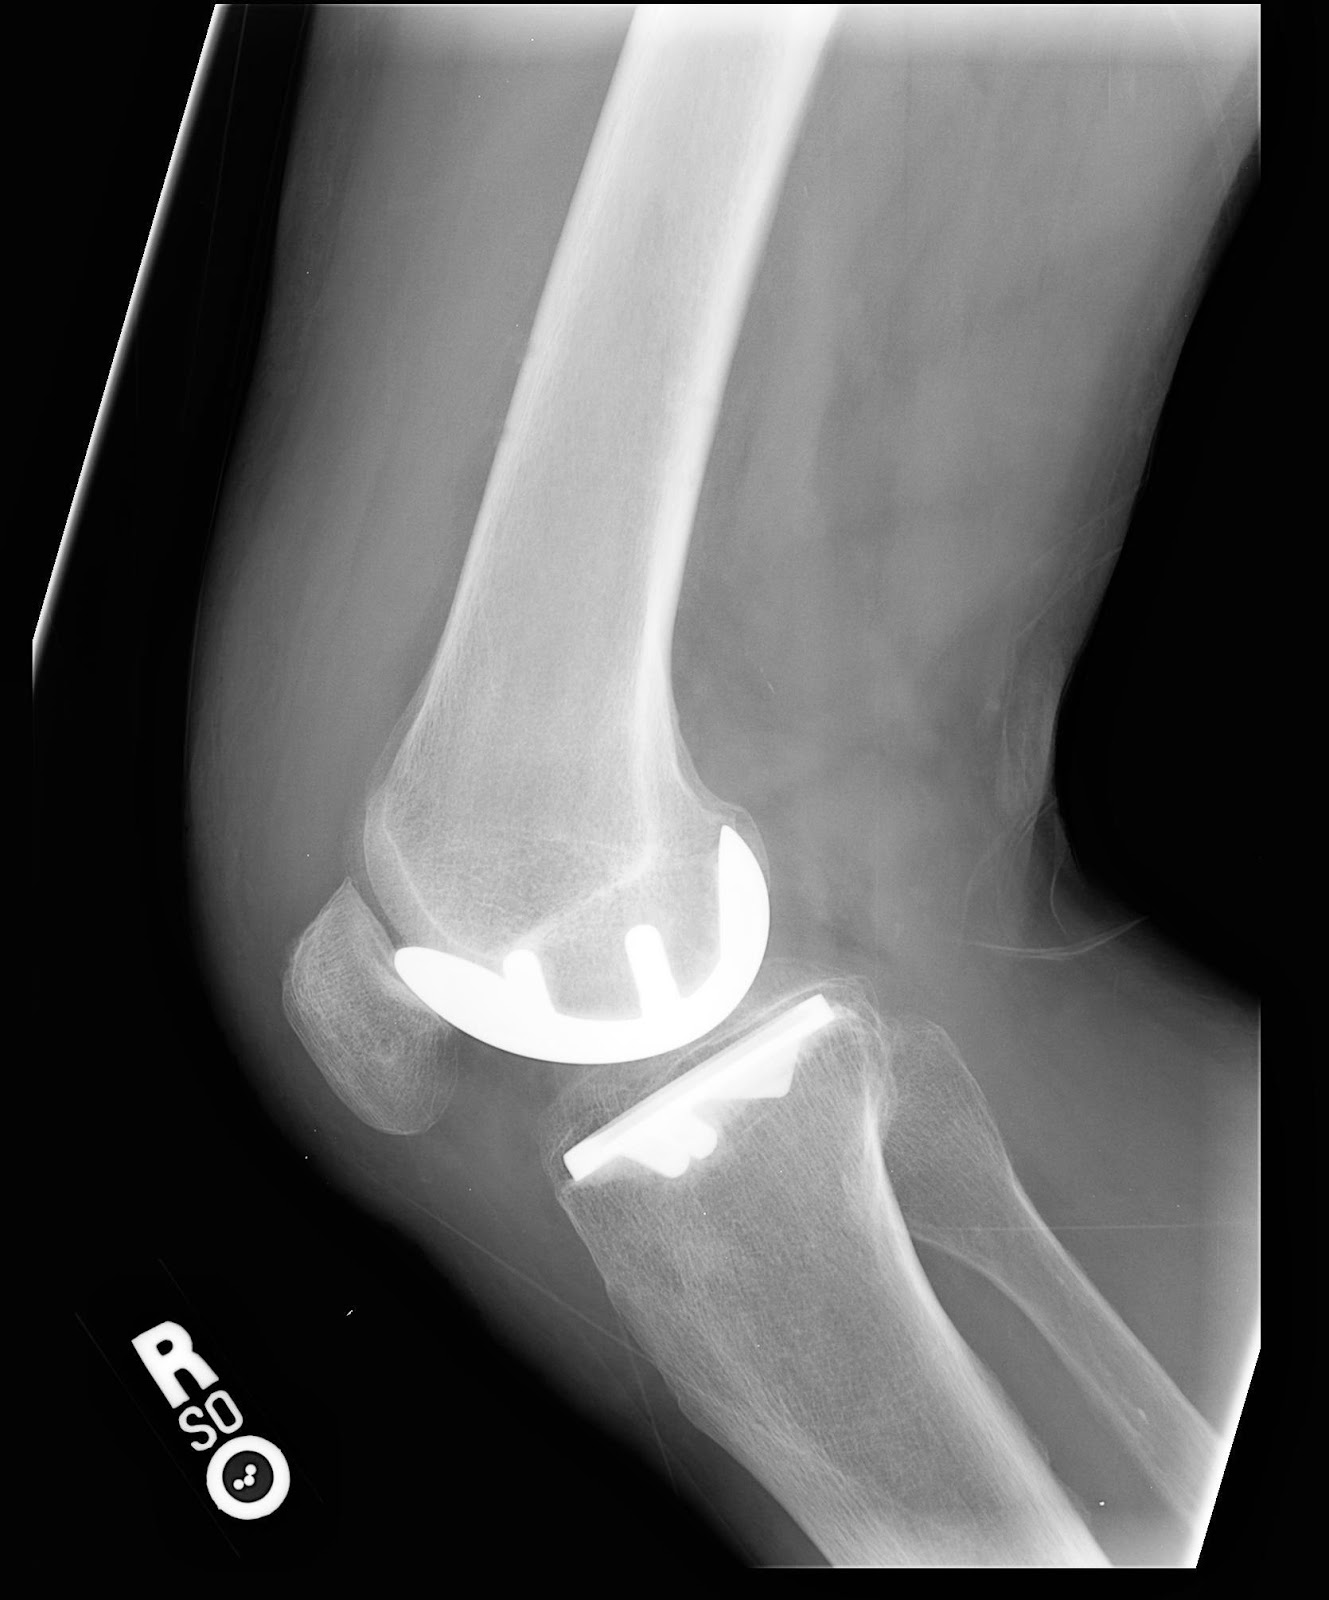

Ortho Xray Knee replacement | MSO Physiotherapy

Knee Replacement, X-ray Photograph by